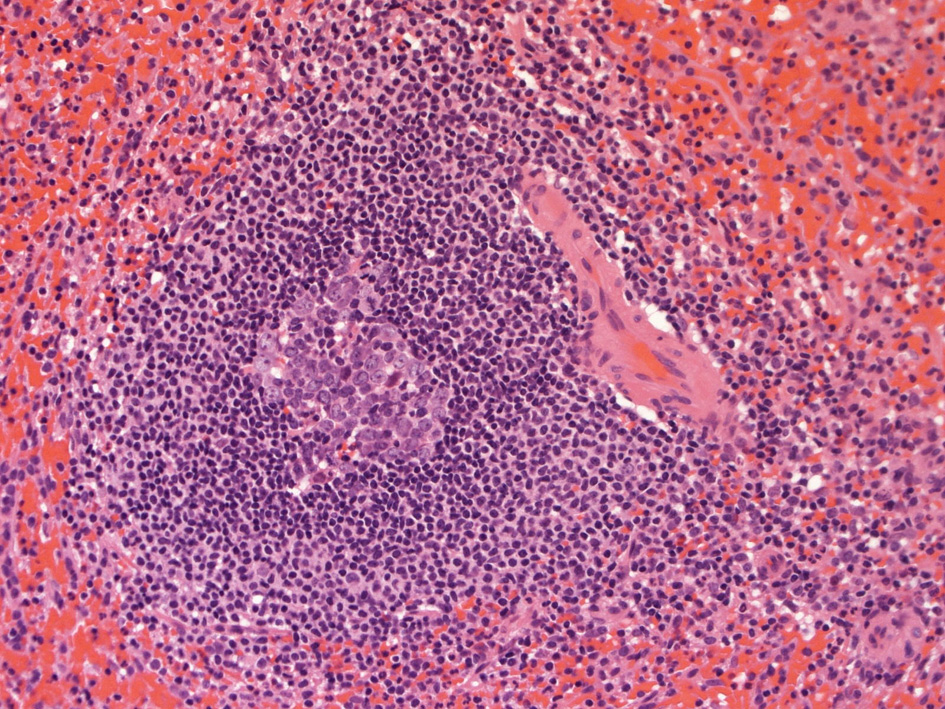

白脾髄の構造

脾動脈脾柱という結合組織を通って実質内に入るところから毛細血管に至るところまで、その周囲にリンパ鞘が形成され、所々にリンパ濾胞が発達しています。(リンパ鞘=PALSと呼ぶ peri-arterial lymphatic sheathの略)

これらの濾胞内には胚中心が見られることが多い。胚中心の周りには暗調にそまる小型のリンパ球がマントル層を作って取り囲んでいます。リンパ鞘もリンパ節の構造と同じく粗で不規則な細網線維からできたネットワークが骨格となっている。

リンパ鞘はT細胞領域リンパ濾胞はB細胞由来です。PALSのT-cellsは CD4+ cell > CD8+ T-cells

胚中心が多数出現しているときはなんらかの抗原刺激を受けたと考えられる.

慢性感染症がある人の脾臓や特発性血小板減少性紫斑病の人の脾臓では胚中心が特に発達してみられます。一方で自己免疫性溶血性貧血では胚中心は少なく、先天性球状赤血球症ではほとんど見られません。

白脾髄の構造 Structure of the white pulp